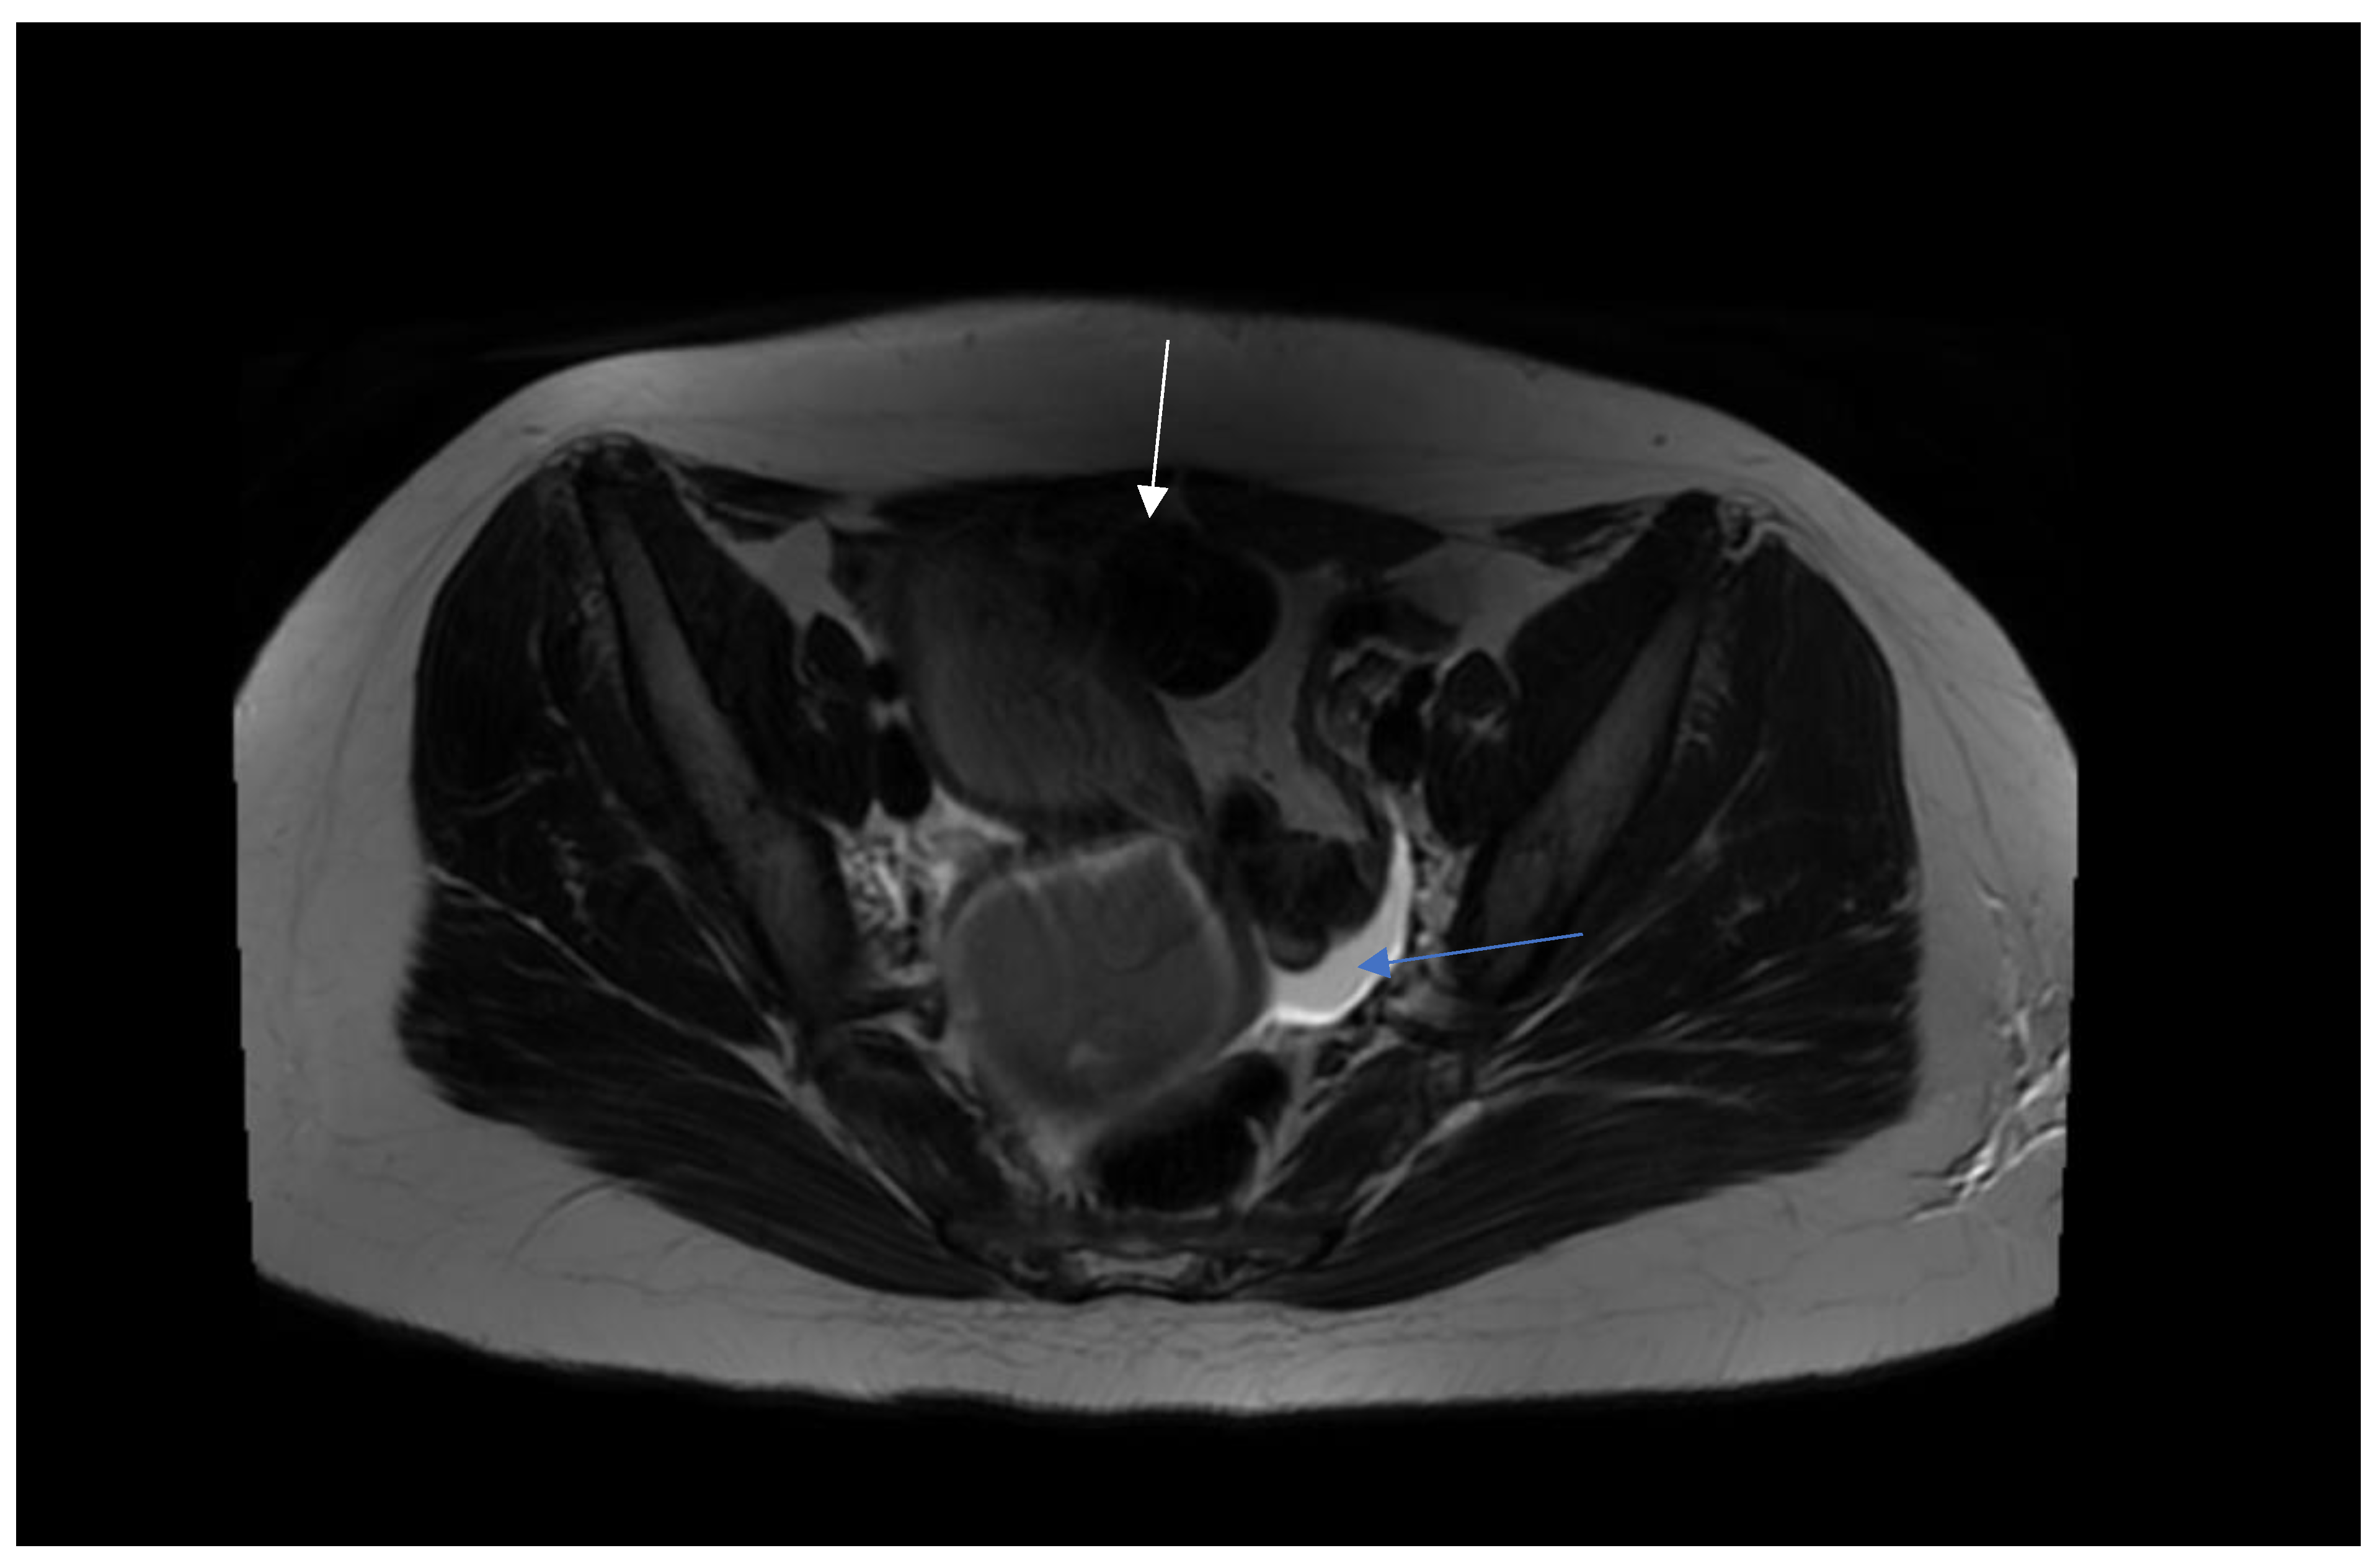

Step 1. Preoperative management Patients age (mostly occurs in young females), accurate history: time of first period, gradually increased symptoms, the appearance of symptoms during menarche, symptoms increase with each subsequent period, recurrent UTI, urinary disorders [8,9]. Perform physical examination. Next to the transabdominal US, transperineal and transrectal US can be useful in emergency situations to accurately access the place of abnormality [10]. MRI imaging should be considered as "gold standard in the diagnostic process [11]. Plan of the surgery and step by step proceeding is important while operating patients with urogenital abnormalities. As interdisciplinary collaboration of urologist and gynecologist is often necessary to treat correctly these patients. |